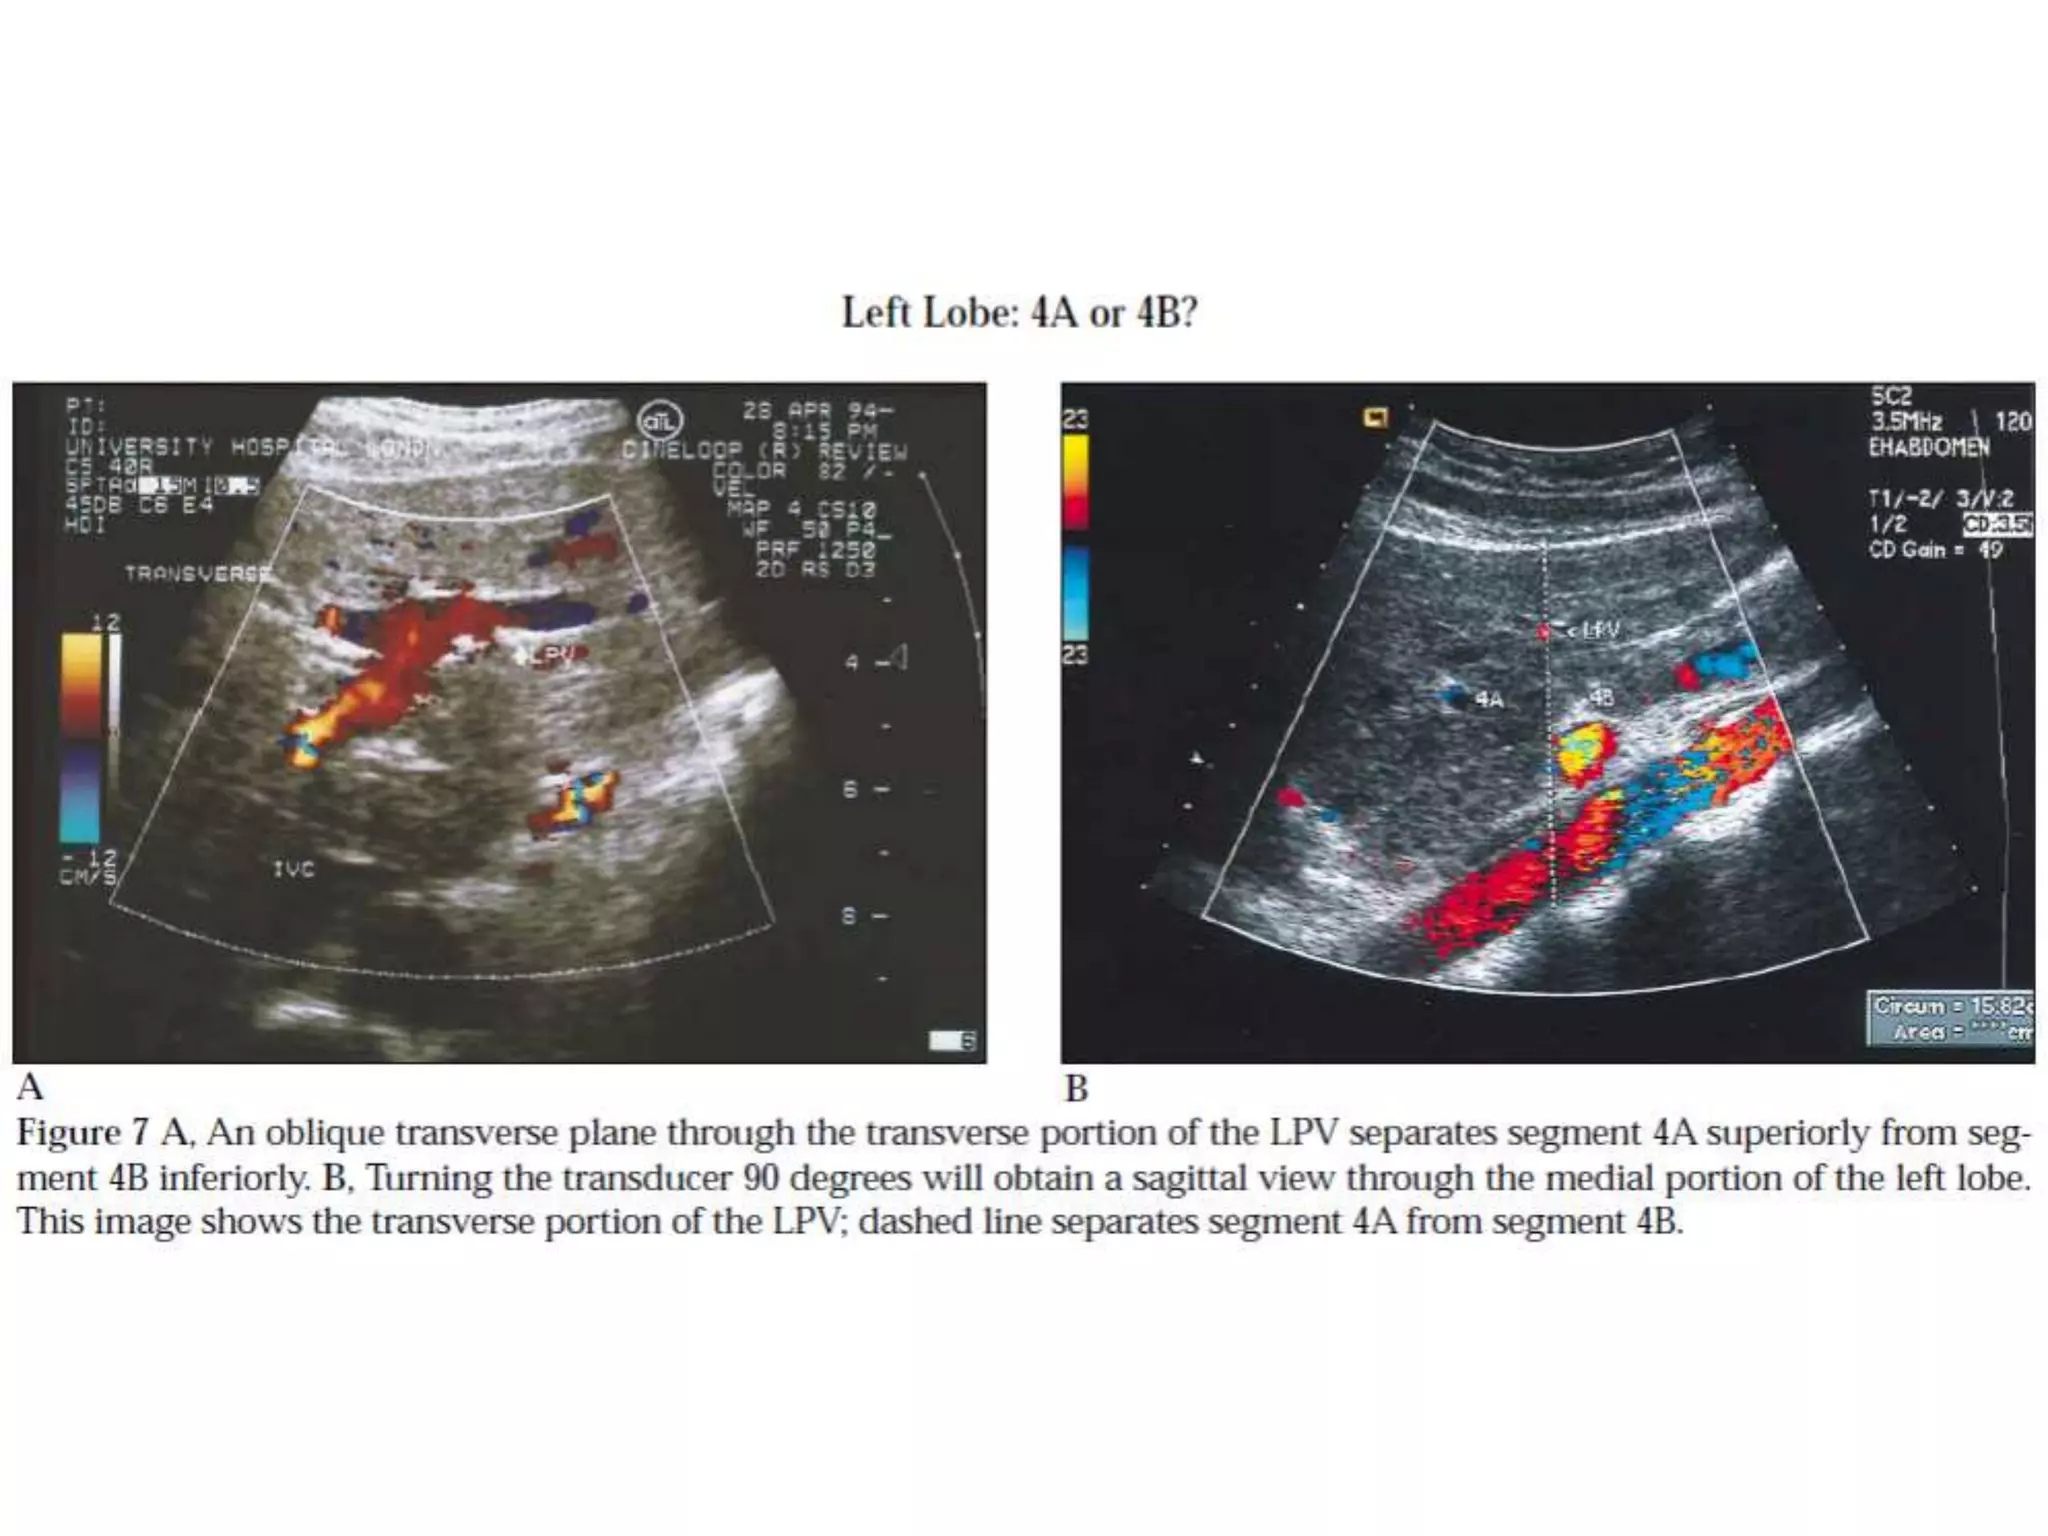

How to separate liver segments

on cross sectional imaging

Left lobe: lateral(II/III) vs

medial segment (IVA/B)

Extrapolate a line along the falciform

ligament superiorly to the confluence

of the left and middle hepatic veins at

the IVC (blue line).